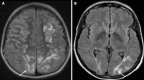

In this editorial, we talk about a compelling case focusing on posterior reversible encephalopathy syndrome (PRES) as a complication in patients undergoing liver transplantation and treated with Tacrolimus. Tacrolimus (FK 506), derived from Streptomyces tsukubaensis, is a potent immunosuppressive macrolide. It inhibits T-cell transcription by binding to FK-binding protein, and is able to amplify glucocorticoid and progesterone effects. Tacrolimus effectively prevents allograft rejection in transplant patients but has adverse effects such as Tacrolimus-related PRES. PRES presents with various neurological symptoms alongside elevated blood pressure, and is primarily characterized by vasogenic edema on neuroimaging. While computed tomography detects initial lesions, magnetic resonance imaging, especially the Fluid-Attenuated Inversion Recovery sequence, is superior for diagnosing cortical and subcortical edema. Our discussion centers on the incidence of PRES in solid organ transplant recipients, which ranges between 0.5 to 5 +ACU-, with varying presentations, from seizures to visual disturbances. The case of a 66-year-old male status post liver transplantation highlights the diagnostic and management challenges associated with Tacrolimus-related PRES. Radiographically evident in the parietal and occipital lobes, PRES underlines the need for heightened vigilance among healthcare providers. This editorial emphasizes the importance of early recognition, accurate diagnosis, and effective management of PRES to optimize outcomes in liver transplant patients. The case further explores the balance between the efficacy of immunosuppression with Tacrolimus and its potential neurological risks, underlining the necessity for careful monitoring and intervention strategies in this patient population.